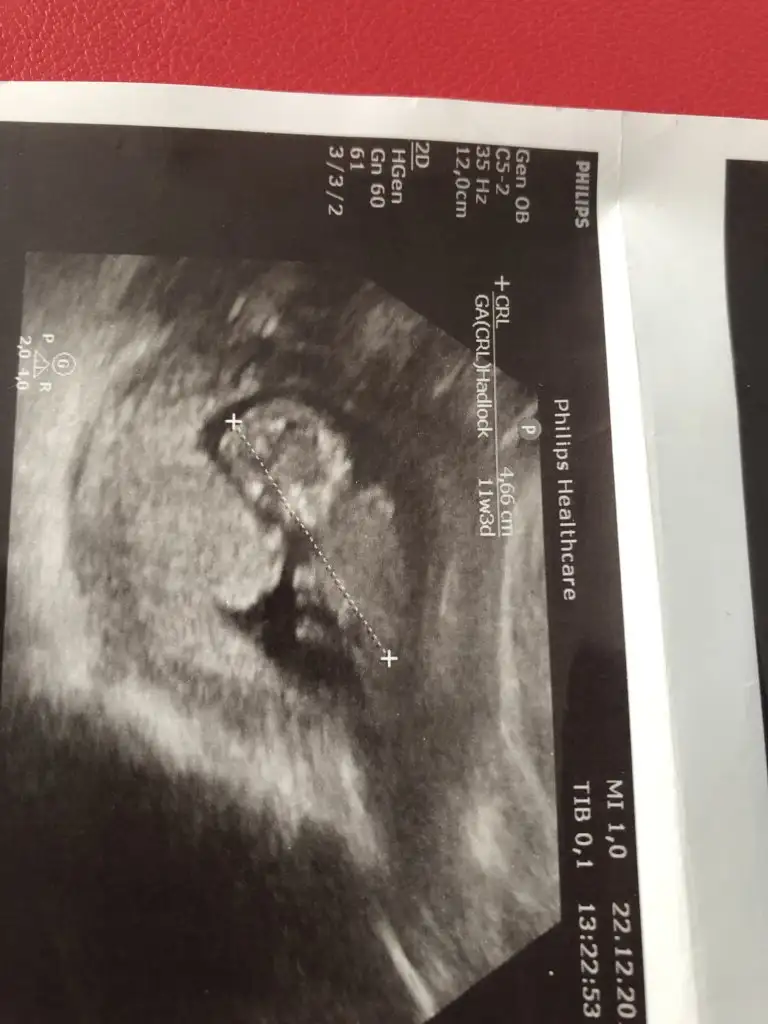

Slm güzel anneler bizde 11+1haftalik olduk bizede bir tahmin edermisiniz

11 yada 12 hafta olmalıbi de benim minnoşuma bakar mısınız vajinal muayane 9 haftalık burda

birde bu şekilde var canımNet degil gördüğüm diklik nub ise erkek gibi ama eminde değilim başka usg varmı 11 yada 12 hafta